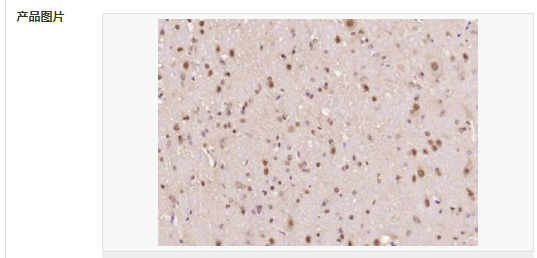

| 產(chǎn)品應(yīng)用 | ELISA=1:5000-10000 IHC-P=1:100-500 IHC-F=1:100-500 ICC=1:100-500 IF=1:100-500 (石蠟切片需做抗原修復(fù)) not yet tested in other applications. optimal dilutions/concentrations should be determined by the end user. |

| 細胞定位 | 細胞核 細胞漿 |

| 產(chǎn)品介紹 | The human ataxin-7 gene, also known as spinocerebellar ataxia 7 or SCA7, maps to chromosome 3p13-p12, has a 2,727-bp open reading frame, and encodes a 892 amino acid protein containing a nuclear localization signal and a polyglutamine tract (1,2). SCA7 is an autosomal dominant neurodegenerative disorder characterized by ataxia and selective neuronal cell loss caused by the expansion of a translated CAG repeat encoding a polyglutamine tract in ataxin-7, which is the SCA7 gene product (3,4). Ataxin-7 is expressed within neurons both affected and unaffected in SCA7 pathology with subcellular localization being variable depending upon the neuronal subtype (5). Polyglutamine expanded in ataxin-7 may carry out its pathogenic effects in the nucleus by altering the matrix-associated nuclear structure and/or by disrupting nucleolar function (6). Function: Ataxin 7 is a protein of unknown function. It may be the human orthologue of the yeast SAGA SGF73 subunit and a subunit of the human TFTC-like transcriptional complexes. Spinocerebellar ataxia 7 (one of a group of hereditary neurodegenrative diseases) is caused by an expanded trinucleotide repeat in the gene encoding ataxin 7. Ataxin 7 is typically located in the cytoplasm and on the nuclear membrane of normal brain neurons. In cells where there is a mutation of the SCA7 gene, ataxin 7 accumulates in intranuclear inclusions and can result in cell death. Subunit: Component of the STAGA transcription coactivator-HAT complex, at least composed of SUPT3H, GCN5L2, TAF5L, TAF6L, SUPT7L, TADA3L, TAD1L, TAF10, TAF12, TRRAP, TAF9 and ATXN7. The STAGA core complex is associated with a subcomplex required for histone deubiquitination composed of ATXN7L3, ENY2 and USP22. Interacts with SORBS1, PSMC1 and CRX. Interacts with TRRAP, GCN5L2 and TAF10. Interacts with alpha tubulin. Subcellular Location: Cytoplasmic (isoform b) and Nuclear (isoform a) Tissue Specificity: Isoform a and isoform b are expressed in CNS, but isoform a is expressed predominantly in the peripherical tissues. Isoform b is also highly expressed in the frontal lobe, skeletal muscle and spinal cord and is expressed at a lower level in the lung, lymphoblast and intestine. Post-translational modifications: Proteolytically cleaved. The cleavage may be involved in SCA7 degeneration: the isoform fragments may exert distinct toxic influences that could contribute to selective neurodegeneration. Sumoylation decreases the aggregation propensity and cellular toxicity of forms with an expanded poly-Gln region but has no effect on subcellular location or interaction with components of the STAGA complex. DISEASE: Defects in ATXN7 are the cause of spinocerebellar ataxia type 7 (SCA7) [MIM:164500]; also known as olivopontocerebellar atrophy III (OPCA III or OPCA3) or olivopontocerebellar atrophy with retinal degeneration. Spinocerebellar ataxia is a clinically and genetically heterogeneous group of cerebellar disorders. Patients show progressive incoordination of gait and often poor coordination of hands, speech and eye movements, due to degeneration of the cerebellum with variable involvement of the brainstem and spinal cord. SCA7 belongs to the autosomal dominant cerebellar ataxias type II (ADCA II) which are characterized by cerebellar ataxia with retinal degeneration and pigmentary macular dystrophy. Similarity: Belongs to the ataxin-7 family. Contains 1 SCA7 domain. SWISS: O15265 Gene ID: 6314 Database links: Entrez Gene: 6314 Human Entrez Gene: 246103 Mouse Omim: 164500 Human Omim: 607640 Human SwissProt: O15265 Human SwissProt: Q8R4I1 Mouse Unigene: 476595 Human Important Note: This product as supplied is intended for research use only, not for use in human, therapeutic or diagnostic applications. |